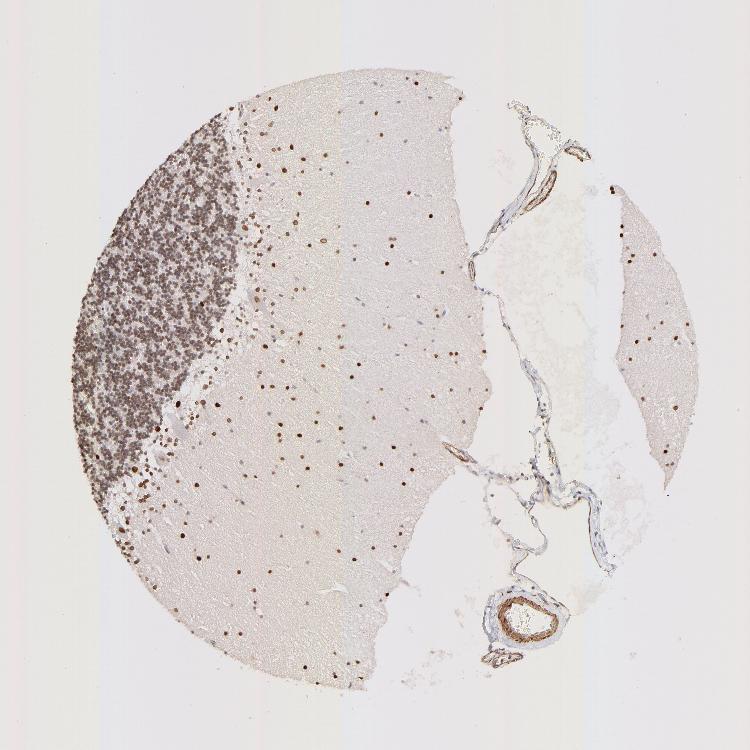

CEREBELLUM - Antibody stainingi

Antibody staining in the annotated cell types in the current human tissue is reported as not detected, low, medium, or high, based on conventional immunohistochemistry profiling in selected tissues. This score is based on the combination of the staining intensity and fraction of stained cells.

Each image is clickable and will lead to virtual microscopy that enables deeper exploration of all samples and also displays staining intensity scores, fraction scores and subcellular localization as well as patient and tissue information for each sample.

Antibody HPA003030

Purkinje cells High

Cells in granular layer Low

Cells in molecular layer High